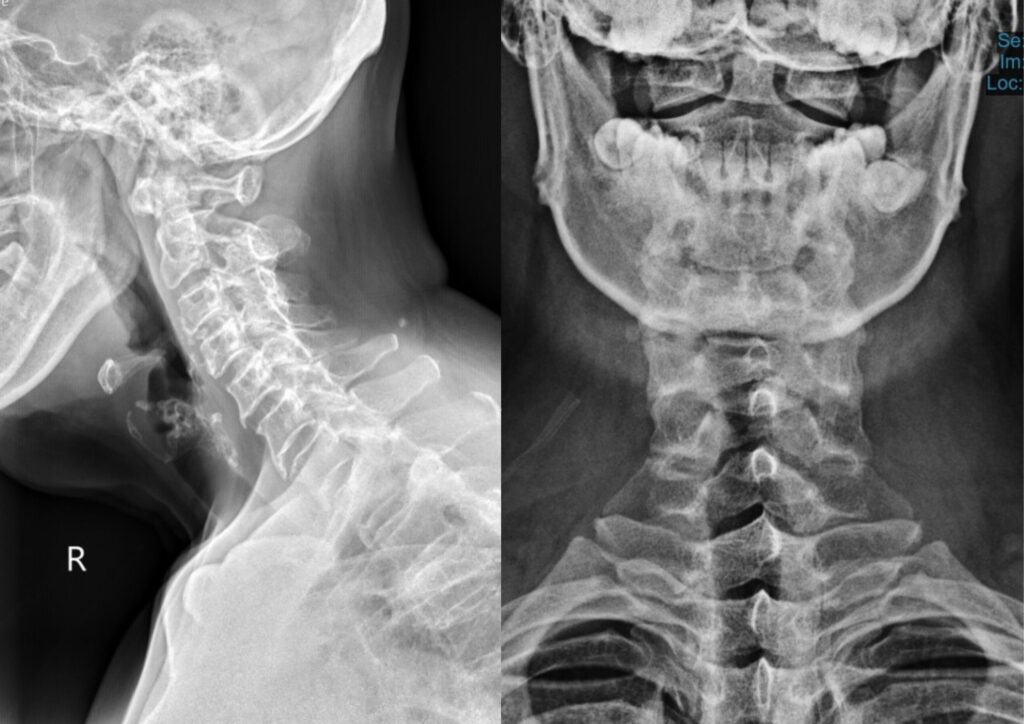

4.Spinal X-rays

(If Required)

In some cases, we may prescribe spinal X-rays to confirm the diagnosis. They tell us how severe the possible misalignments are, and if there are any complicating factors present.